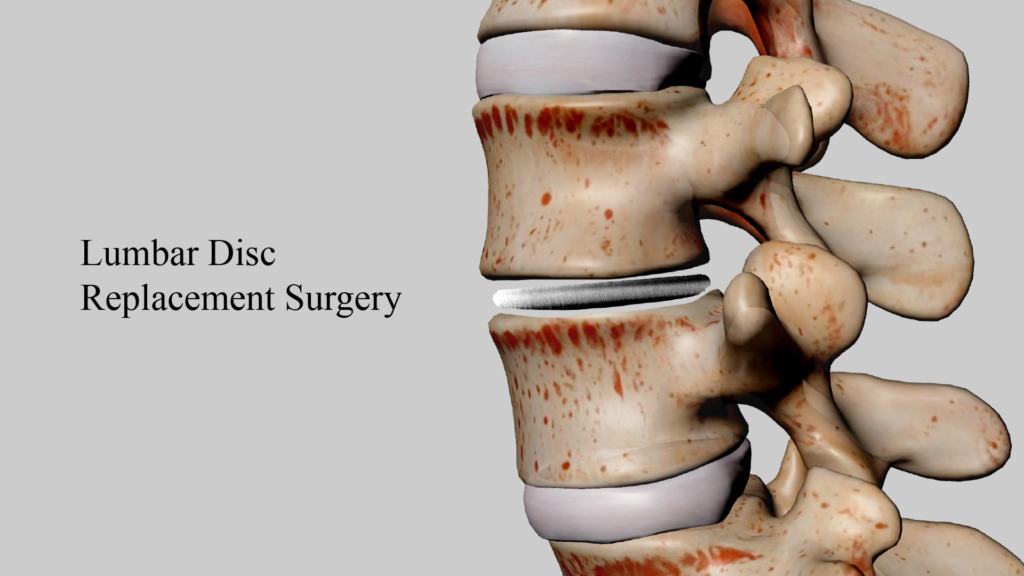

Lumbar disc replacement (LDR) is a surgical procedure designed to address degenerative or damaged lumbar discs. This technique offers a new treatment option for patients suffering from chronic back pain, providing better mobility retention and faster recovery compared to traditional spinal fusion surgery.

The fundamental principle of lumbar disc replacement surgery involves removing the damaged disc and replacing it with an artificial disc. These artificial discs are typically made from biocompatible materials such as metal and plastic, designed to mimic the function and range of motion of natural discs. This surgery aims to alleviate pain, restore normal spinal movement, and avoid potential issues associated with traditional fusion surgery.

2. Surgical Process: Under general anesthesia, the surgeon makes a small incision in the patient’s lower back, removes the damaged disc, and implants the artificial disc. The procedure typically takes 1 to 2 hours.